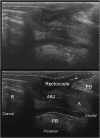

Total pelvic floor ultrasound is used for the dynamic assessment of pelvic floor dysfunction and allows multicompartmental anatomical and functional assessment. Pelvic floor dysfunction includes defaecatory, urinary and sexual dysfunction, pelvic organ prolapse and pain. It is common, increasingly recognized and associated with increasing age and multiparity. Other options for assessment include defaecation proctography and defaecation MRI. Total pelvic floor ultrasound is a cheap, safe, imaging tool, which may be performed as a first-line investigation in outpatients. It allows dynamic assessment of the entire pelvic floor, essential for treatment planning for females who often have multiple diagnoses where treatment should address all aspects of dysfunction to yield optimal results. Transvaginal scanning using a rotating single crystal probe provides sagittal views of bladder neck support anteriorly. Posterior transvaginal ultrasound may reveal rectocoele, enterocoele or intussusception whilst bearing down. The vaginal probe is also used to acquire a 360° cross-sectional image to allow anatomical visualization of the pelvic floor and provides information regarding levator plate integrity and pelvic organ alignment. Dynamic transperineal ultrasound using a conventional curved array probe provides a global view of the anterior, middle and posterior compartments and may show cystocoele, enterocoele, sigmoidocoele or rectocoele. This pictorial review provides an atlas of normal and pathological images required for global pelvic floor assessment in females presenting with defaecatory dysfunction. Total pelvic floor ultrasound may be used with complementary endoanal ultrasound to assess the sphincter complex, but this is beyond the scope of this review.